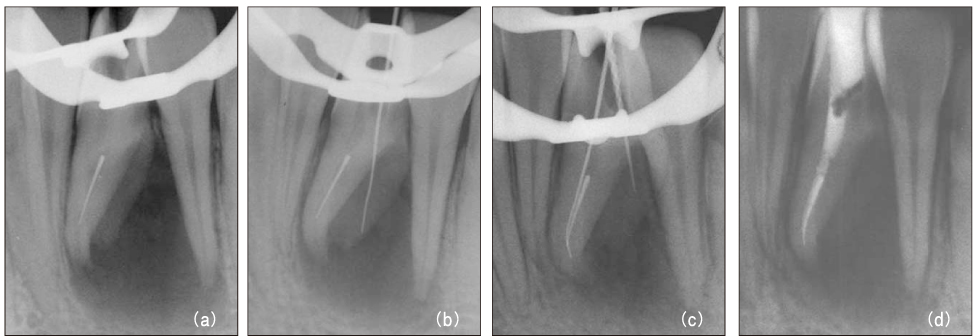

Figure 11

Diagnostic intraoral radiograph (a). By-passing with hand file (b) and canal obturation (c, d). 30-month recall (e): tooth is symptomless.

jkacd-31-161-g011.jpg

Figure 11 Diagnostic intraoral radiograph (a). By-passing with hand file (b) and canal obturation (c, d). 30-month recall (e): tooth is symptomless.